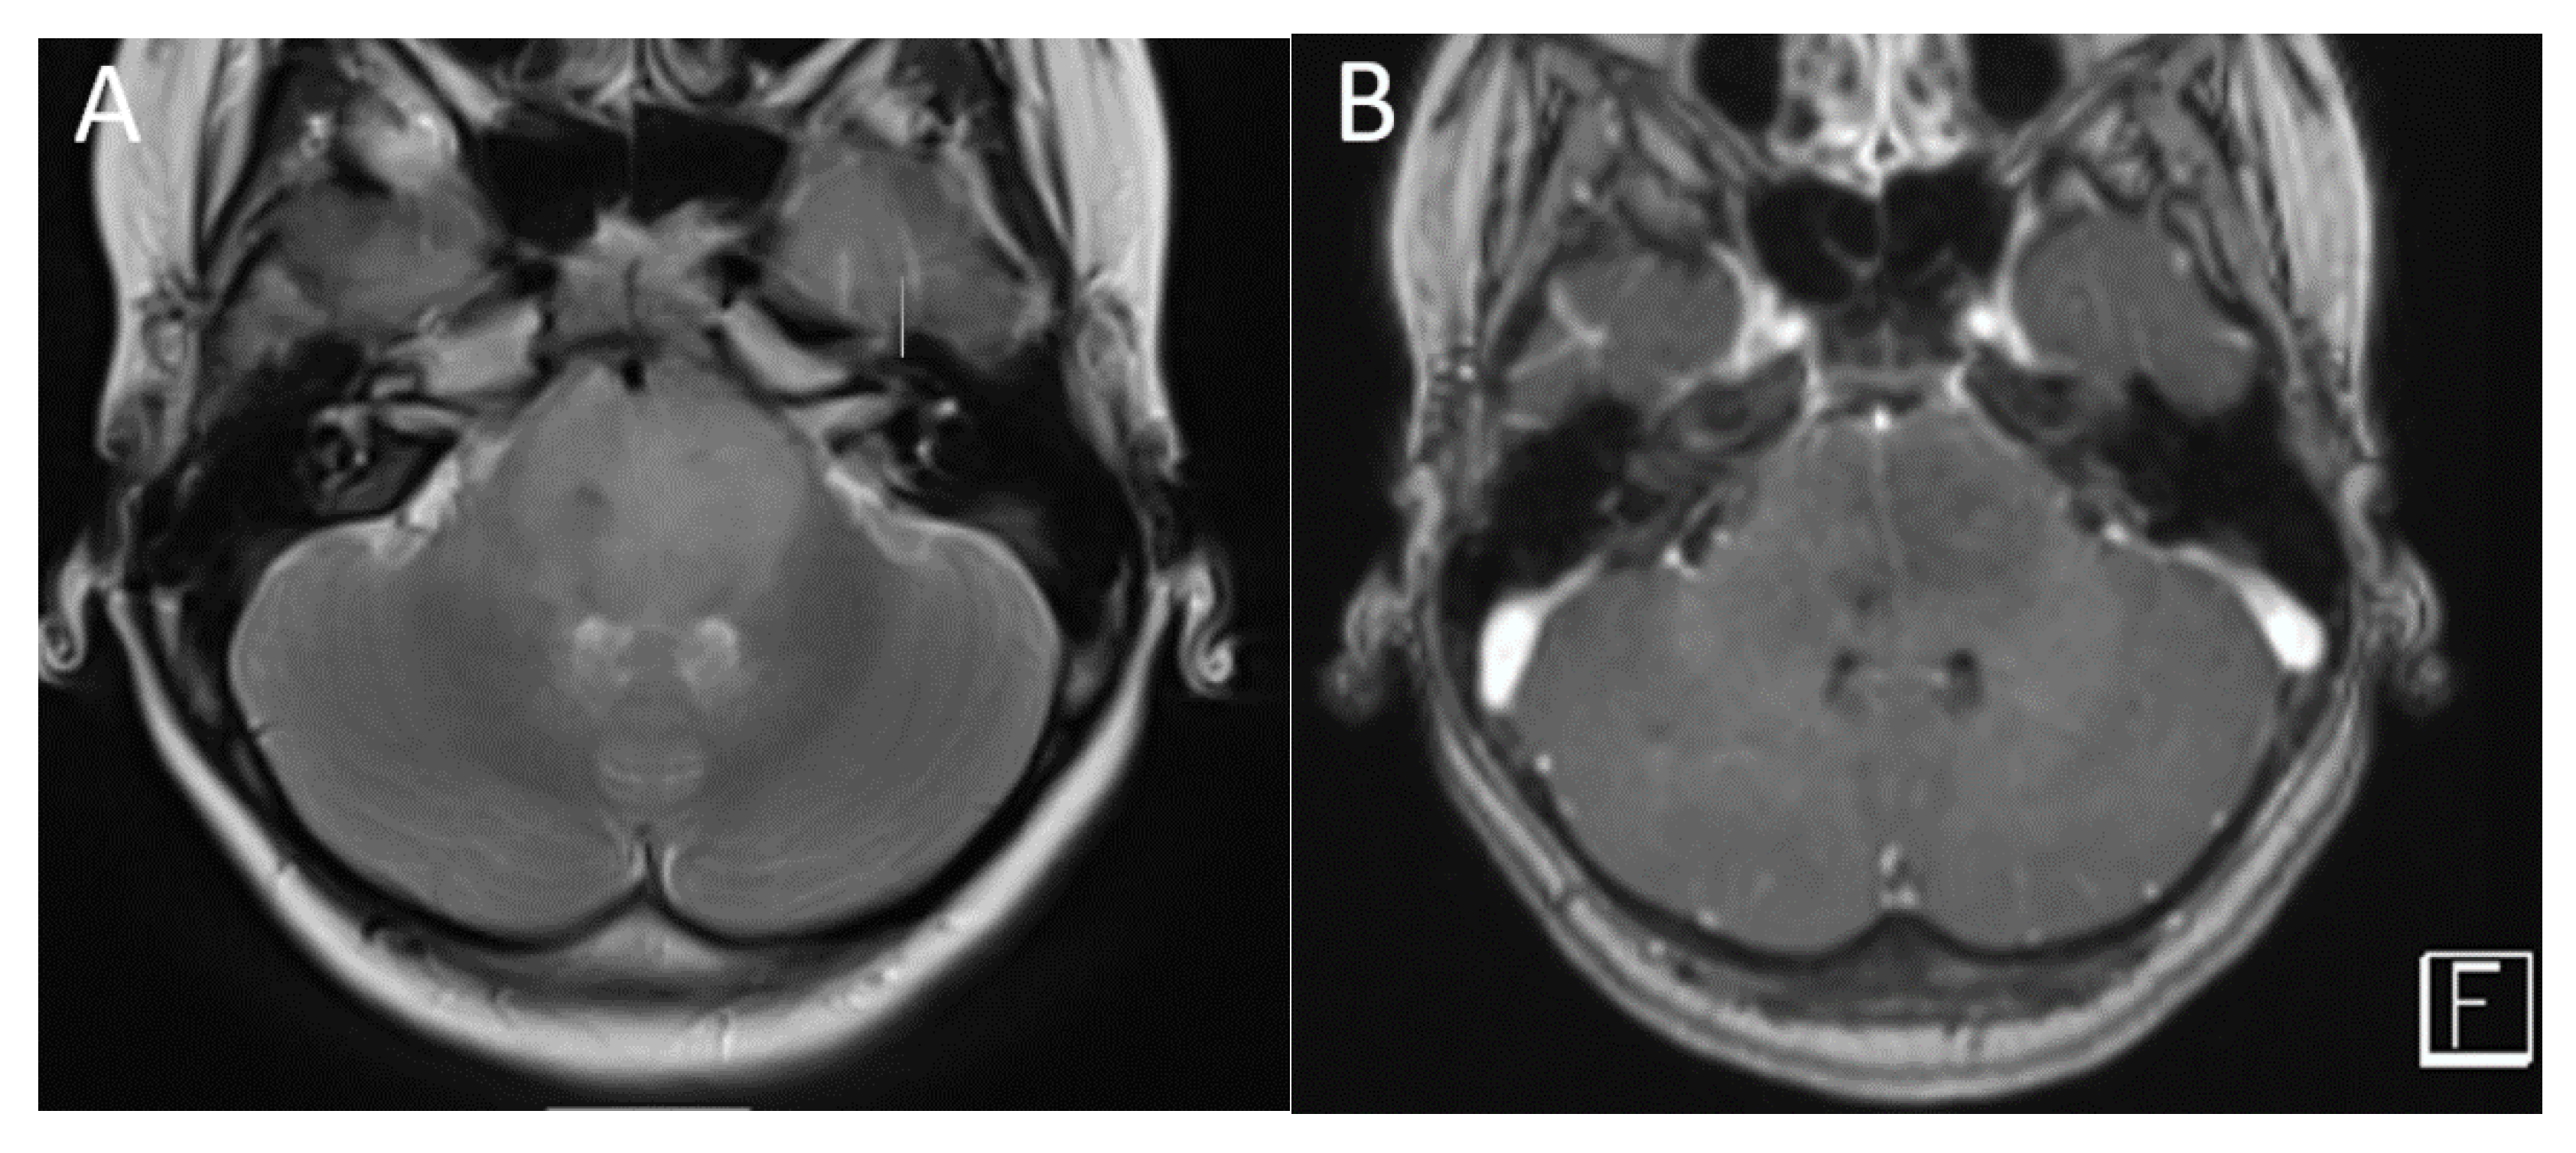

| Medulloblastoma | Exclusively posterior fossa Most commonly in fourth ventricle/cerebellar vermis (non-WNT, non-SHH, or WNT), can involve cerebellopontine angle (WNT) or cerebellar hemispheres with extra-axial extension (SHH) | Diffusion restricting Variable enhancement Cystic/necrotic change may be present Calcifications uncommon Taurine peak characteristic |

| Posterior fossa ependymoma | Fourth ventricle (PFB) or cerebellopontine angle (PFA) | Heterogeneous mass Calcifications common Intermediate diffusion (between medulloblastoma and pilocytic astrocytoma) Usually enhancing High myo-inositol on MRS |